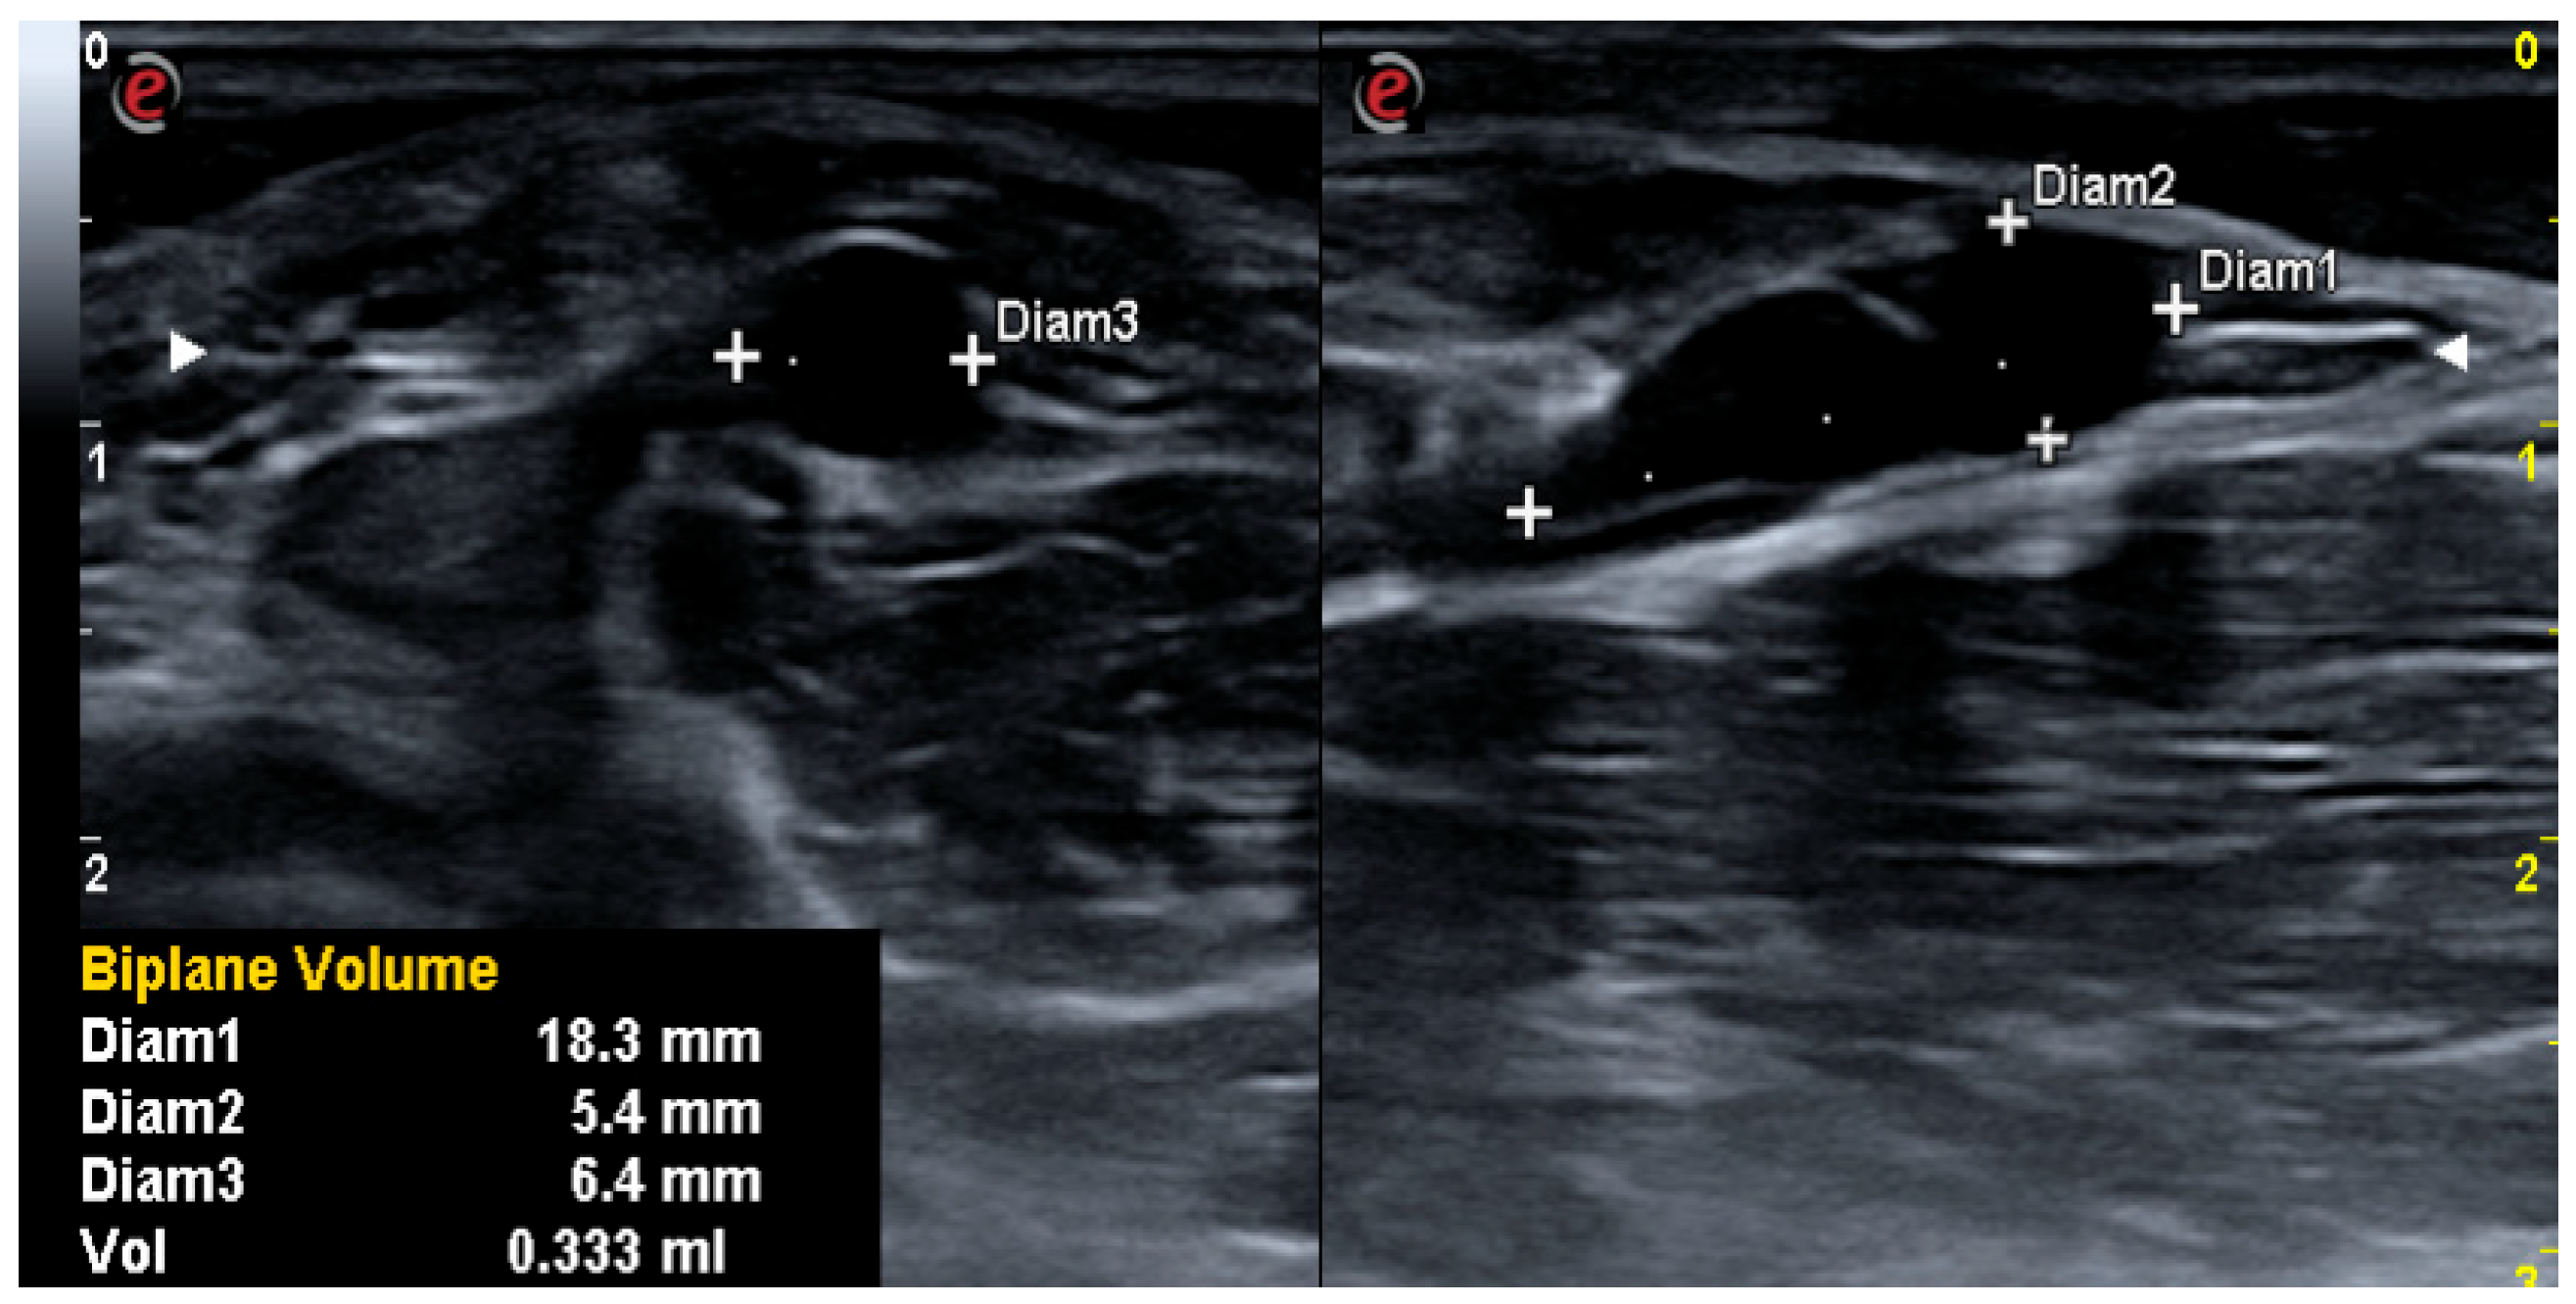

| Echo volume | |||||||||||

| Admission | 1.83 | 0.40 | 2.77 | 0.08–9.6 | 0.26–2.47 | 0.88 | 0.45 | 1.19 | 0.03–4.7 | 0.12–0.84 | 0.205 |

| Discharge | 0.70 | 0.17 | 1.6 | 0.00–7.3 | 0.07–0.48 | 0.51 | 0.23 | 0.69 | 0.02–2.3 | 0.08–0.55 | 0.599 |

| p admission/discharge | 0.000 | 0.003 | |||||||||